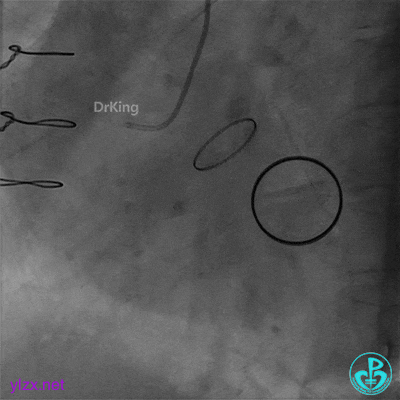

07 10天后复查造影

前降支血栓消失,回旋支恢复3级血流。回旋支夹层?血栓?

没有进一步处理。